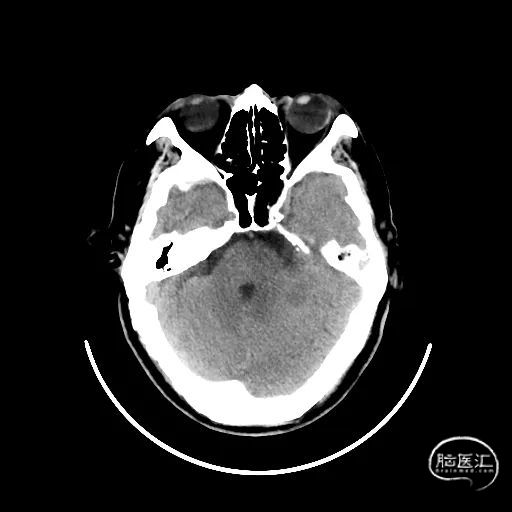

术后造影:

血管再通,前向血流3级。左侧为胚胎型大脑后。

术后用药:替罗非班24小时复查CT后桥接双抗。

术后CT:未见明显脑出血,双侧小脑低密度影。

术后CTA:Bridge药物支架形态良好,前向血流良好。